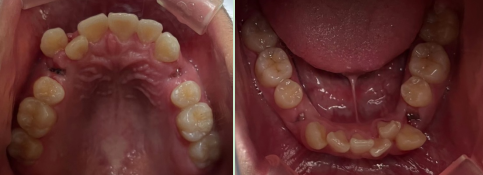

整牙为什么需要拔牙?

1、牙列严重拥挤

2、侧貌凸

3、咬合不良